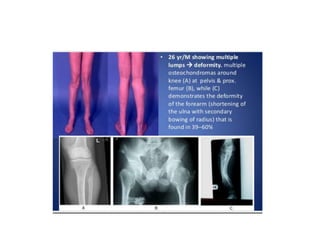

HME associated deformity

Short ulna + radial bowing (39 – 60%)

Limb length inequality ( 8 – 33%)

Varus /Valgus angulation (2 – 54%)

Ankle deformity(2 – 54%)

Disproportionate short stature (37 – 44%)

HME associated deformity Shortulna + radial bowing (39 – 60%) Limb length inequality ( 8 – 33%) Varus /Valgus angulation (2 – 54%) Ankle deformity(2 – 54%) Disproportionate short stature (37 – 44%)